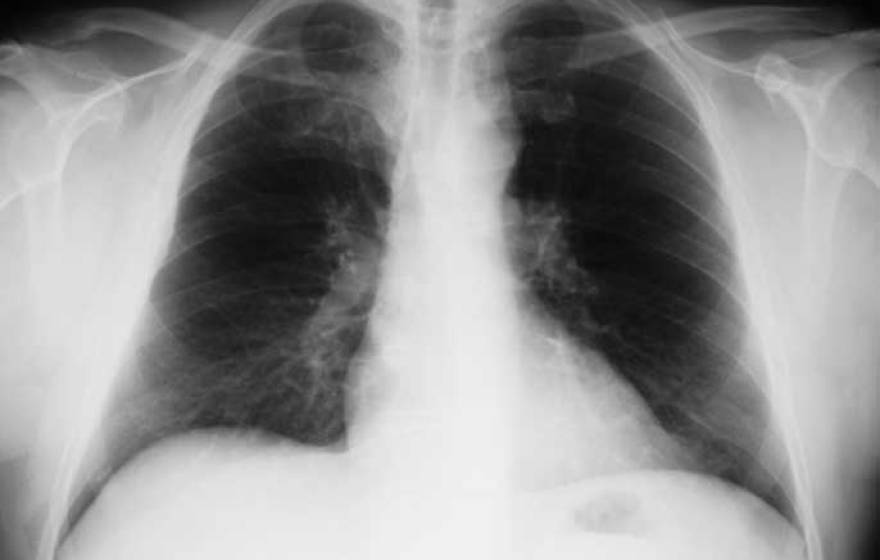

Potential lung cancer vaccine shows renewed promise

In mouse studies, an investigational cancer vaccine boosted immune response and reduced the number of tumors.